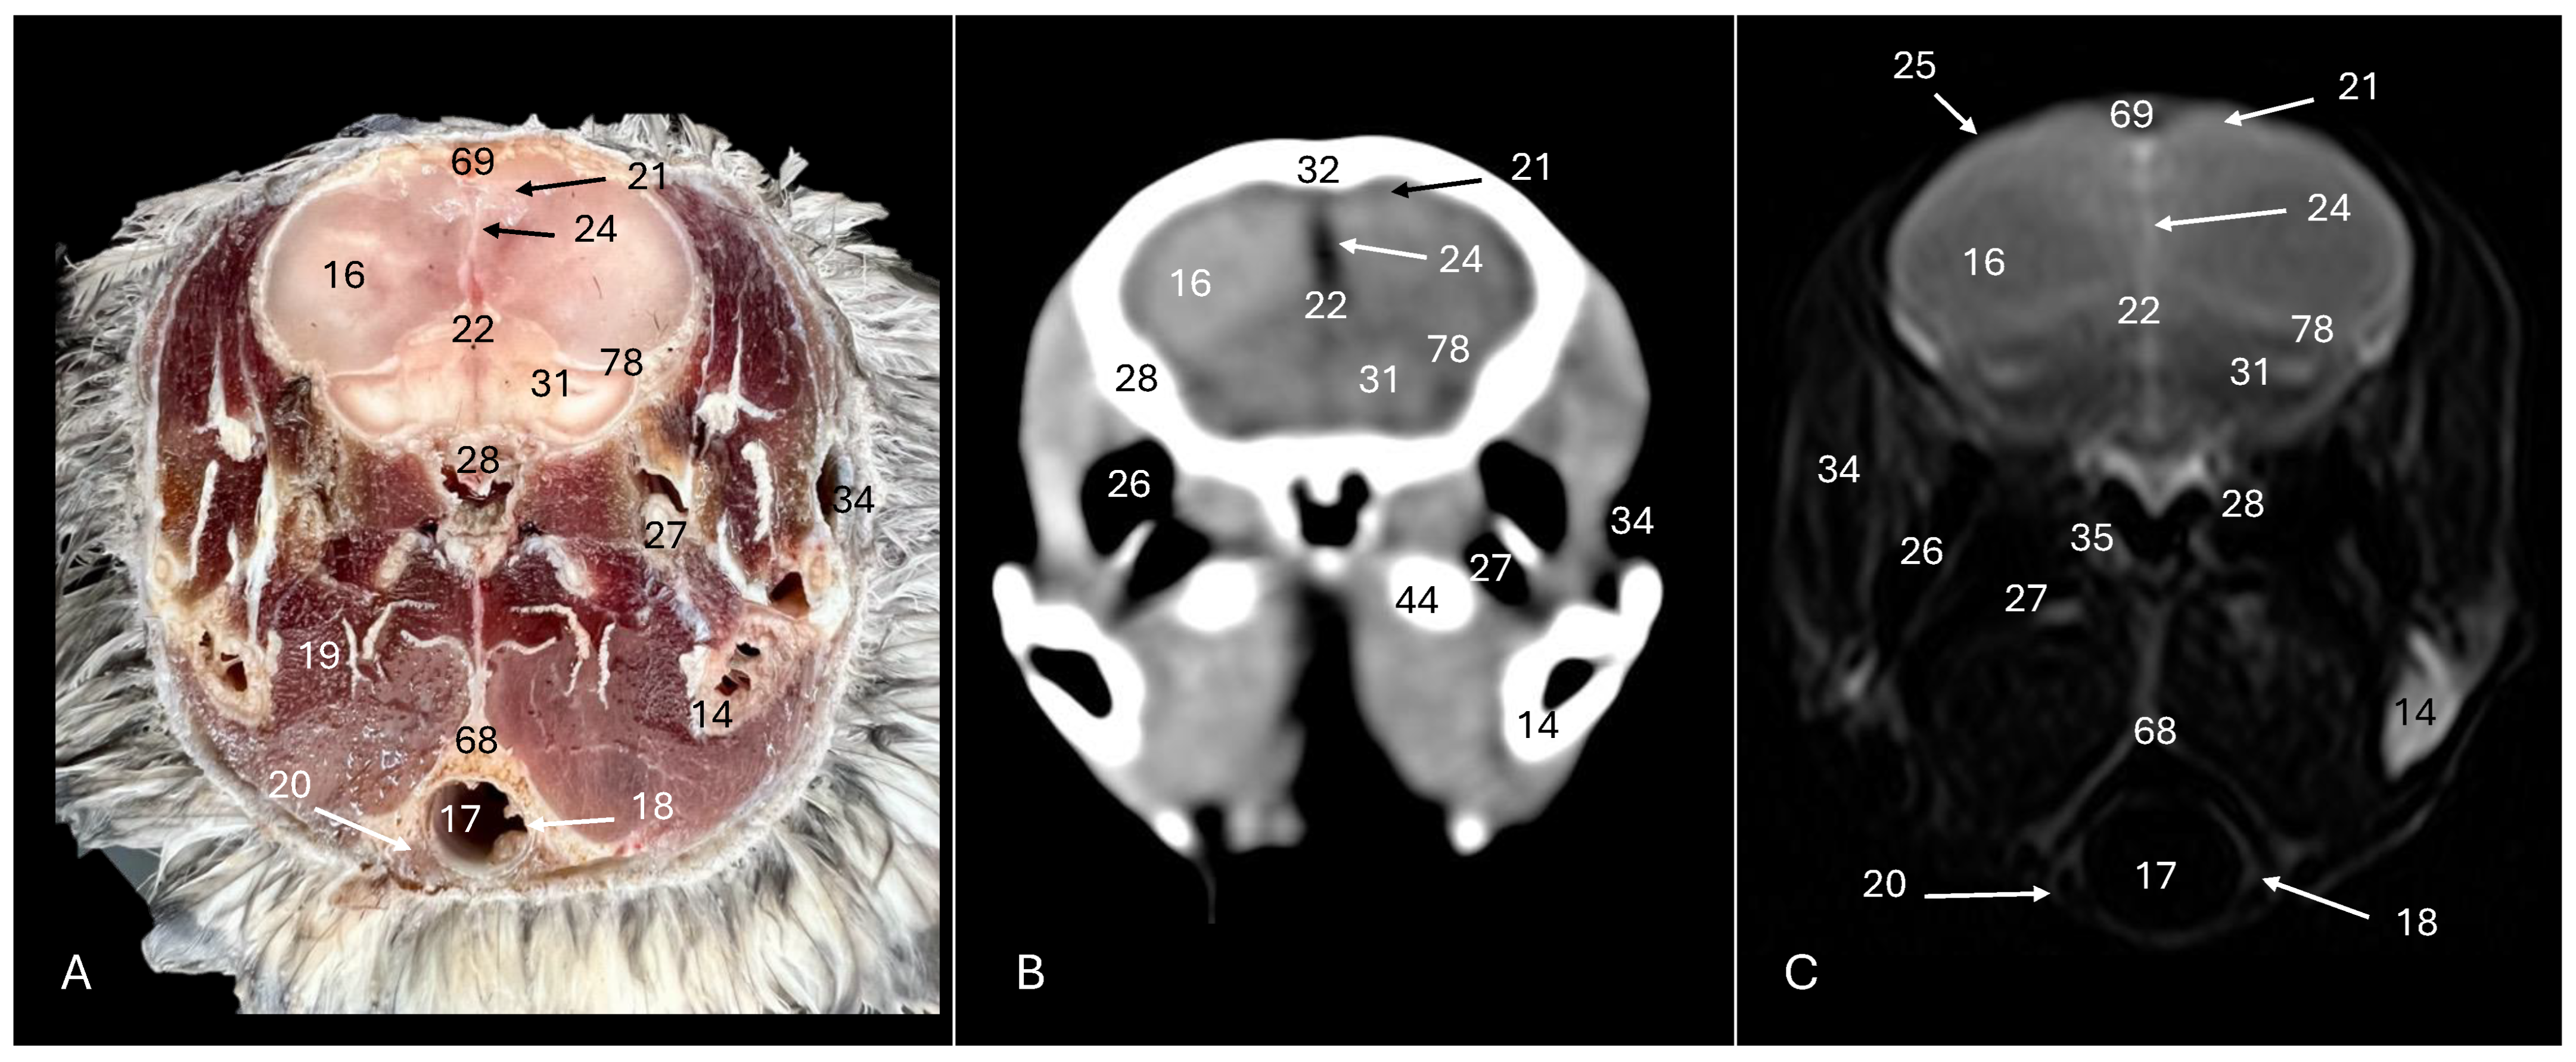

3. Result

3.1. Anatomical Sections

3.2. Computed Tomography (CT)

3.3. Magnetic Resonance Imaging (MRI)